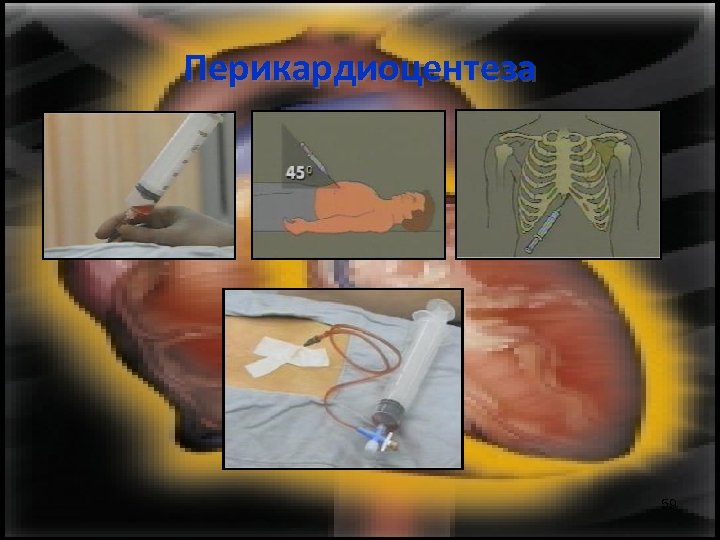

Перикардиоцентеза При доказана диагноза и хемодинамични нарушения се провежда перикардиоцентеза. 58

Перикардиоцентеза 59